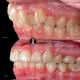

اصلاح همزمان دیپ بایت و زاویه دندانهای قدامی با استفاده از اینتروژن آرچ

Correction of deepbite and front teeth inclination done simultaneously by using intrusion arches